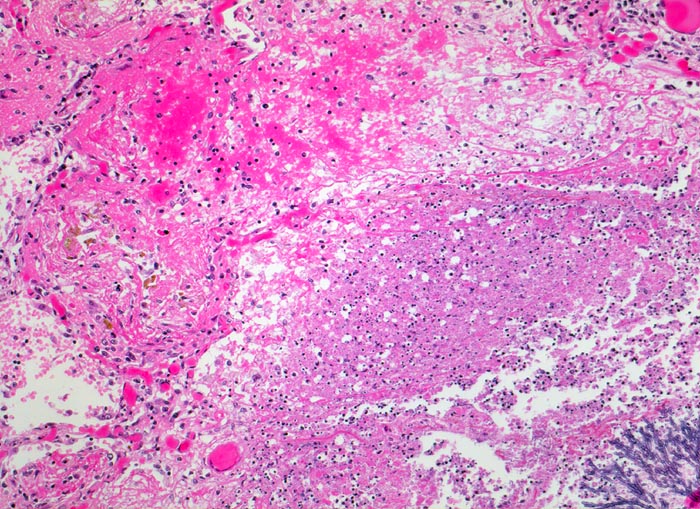

Aspergillus unterscheidet sich von anderen Pilzen (> 1462) (> 712) durch häufige Verzweigungen der Hyphen in einem Winkel von 45°, die radiär in grossen Kolonien liegen (> 547) (> 556). Besonders gut sind die Pilze in der PAS (> 717) und in der Grocott (> 189) Färbung nachweisbar. Die vier häufigsten durch Aspergillen hervorgerufenen Lungenerkrankungen sind die allergische bronchopulmonale Aspergillose, die chronische nekrotisierende Aspergilluspneumonie, das Aspergillom oder wie in diesem Fall die invasive Aspergillose. (Näheres zu den verschiedenen Krankheitsbildern im Literaturlink). Bei Immunsupprimierten invadieren die Pilze häufig die Gefässe. Dies führt zu Infarkten, Blutungen und Nekrosen der Lunge. Über die Invasion der Gefässe kommt es zur septischen Streuung (> 715) (> 49) im grossen Kreislauf.

• Multiple Herde mit zentraler Nekrose und hämorrhagischem Randsaum.

• Pilzmyzelien, zerfallende neutrophile Granulozyten und Erythrozyten im Zentrum der Herde.

• Hämorrhagischer Randsaum um die Nekrose: Hyperämische Alveolarwandkapillaren. Alveolen angefüllt mit Blut, Fibrin und Alveolarmakrophagen.